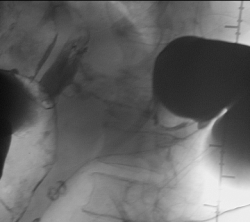

А это что?

А вот, по поводу, наличия дивертикулёза у меня весьма больние сомнения.

То что в нисходящем отделе ободочной кишки-дивертикулез это на 100%, по поводу "сигмы" ещё можно посомниваться, но этот участок попадает под резекцию, у морфологов узнаю, а вот ампула прямой кишки, это да, что как то я сомневаюсь до сих пор что это остаточные каловые массы, пациент подготовлен-отлично, возможно полип, но как бы ещё хуже не оказалось, но в дальнейшем всё равно попадёт к нам на контроль, плюс эндоскописты. Кстати вроде планы ещё резко сменились по ведению этого пациента, думаю хирурги озадачились, хотя трансфузиолог свои запеси уже оставил.